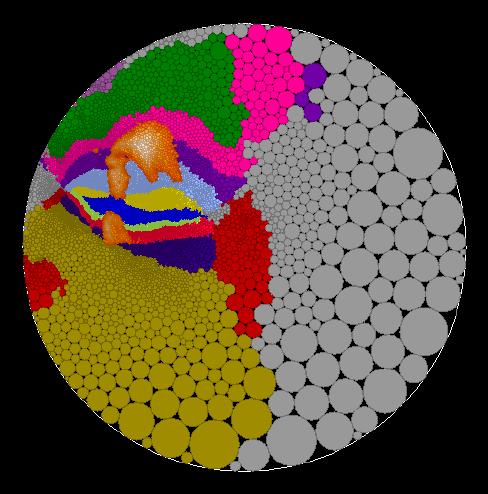

Here are some example of flat maps of the cerebellum which I have created.

This information can be imposed on the flat maps. One of the benefits of

circle packing, is that you can create maps in different geometries, such as

in the Euclidean plane, in the hyperbolic plane or on a sphere. Here is a map

in the Euclidean plane. It shows the various anatomical regions of the

cerebellum and has the functional regions from the target interception task

imposed onto it.